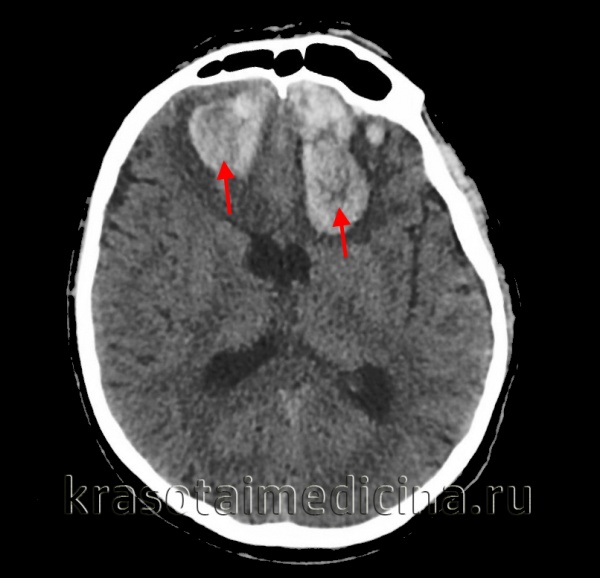

(а) Макропрепарат головного мозга, вид сзади: двустороннее вклинение миндалин мозжечка. Обратите внимание на желобки на миндалинах, сформированные за счет их сдавливания о край большого затылочного отверстия при нисходящей дислокации миндалин по направлению к верхнешейному отделу спинного мозга.

(б) МРТ, Т2-ВИ, аксиальный срез: выраженное вклинение миндалин мозжечка -дислокация обеих миндалин книзу и обтурирация ими просвета большой цистерны со смещением верхнешейного отдела спинного мозга кпереди.